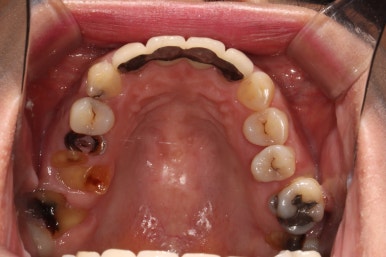

위턱 교합면입니다.

가장 드라마틱하게 바뀐 곳 중 하나인데요,

자기 자리를 잃어버렸던 치아들은 제거되고, 앞니는 지르코니아 크라운과 레진치료로 깨끗한 모습을 되찾았습니다.

썩었던 사랑니도 발치되었고 어금니 부위는 이제 깔끔한 스트라우만 임플란트 + 지르코니아 크라운 조합으로 마무리되었군요.